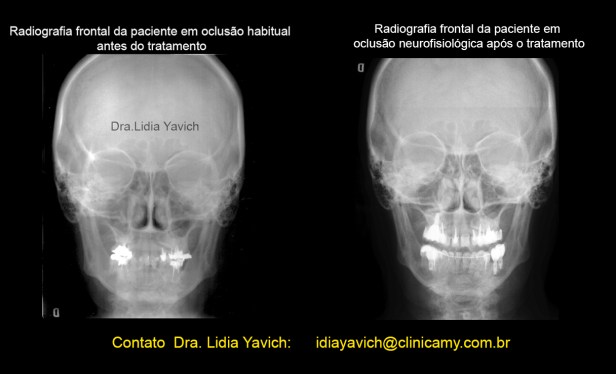

Comparação das radiografias frontais pré e após reabilitação neuromuscular fisiológica e ortodontia tridimensional.